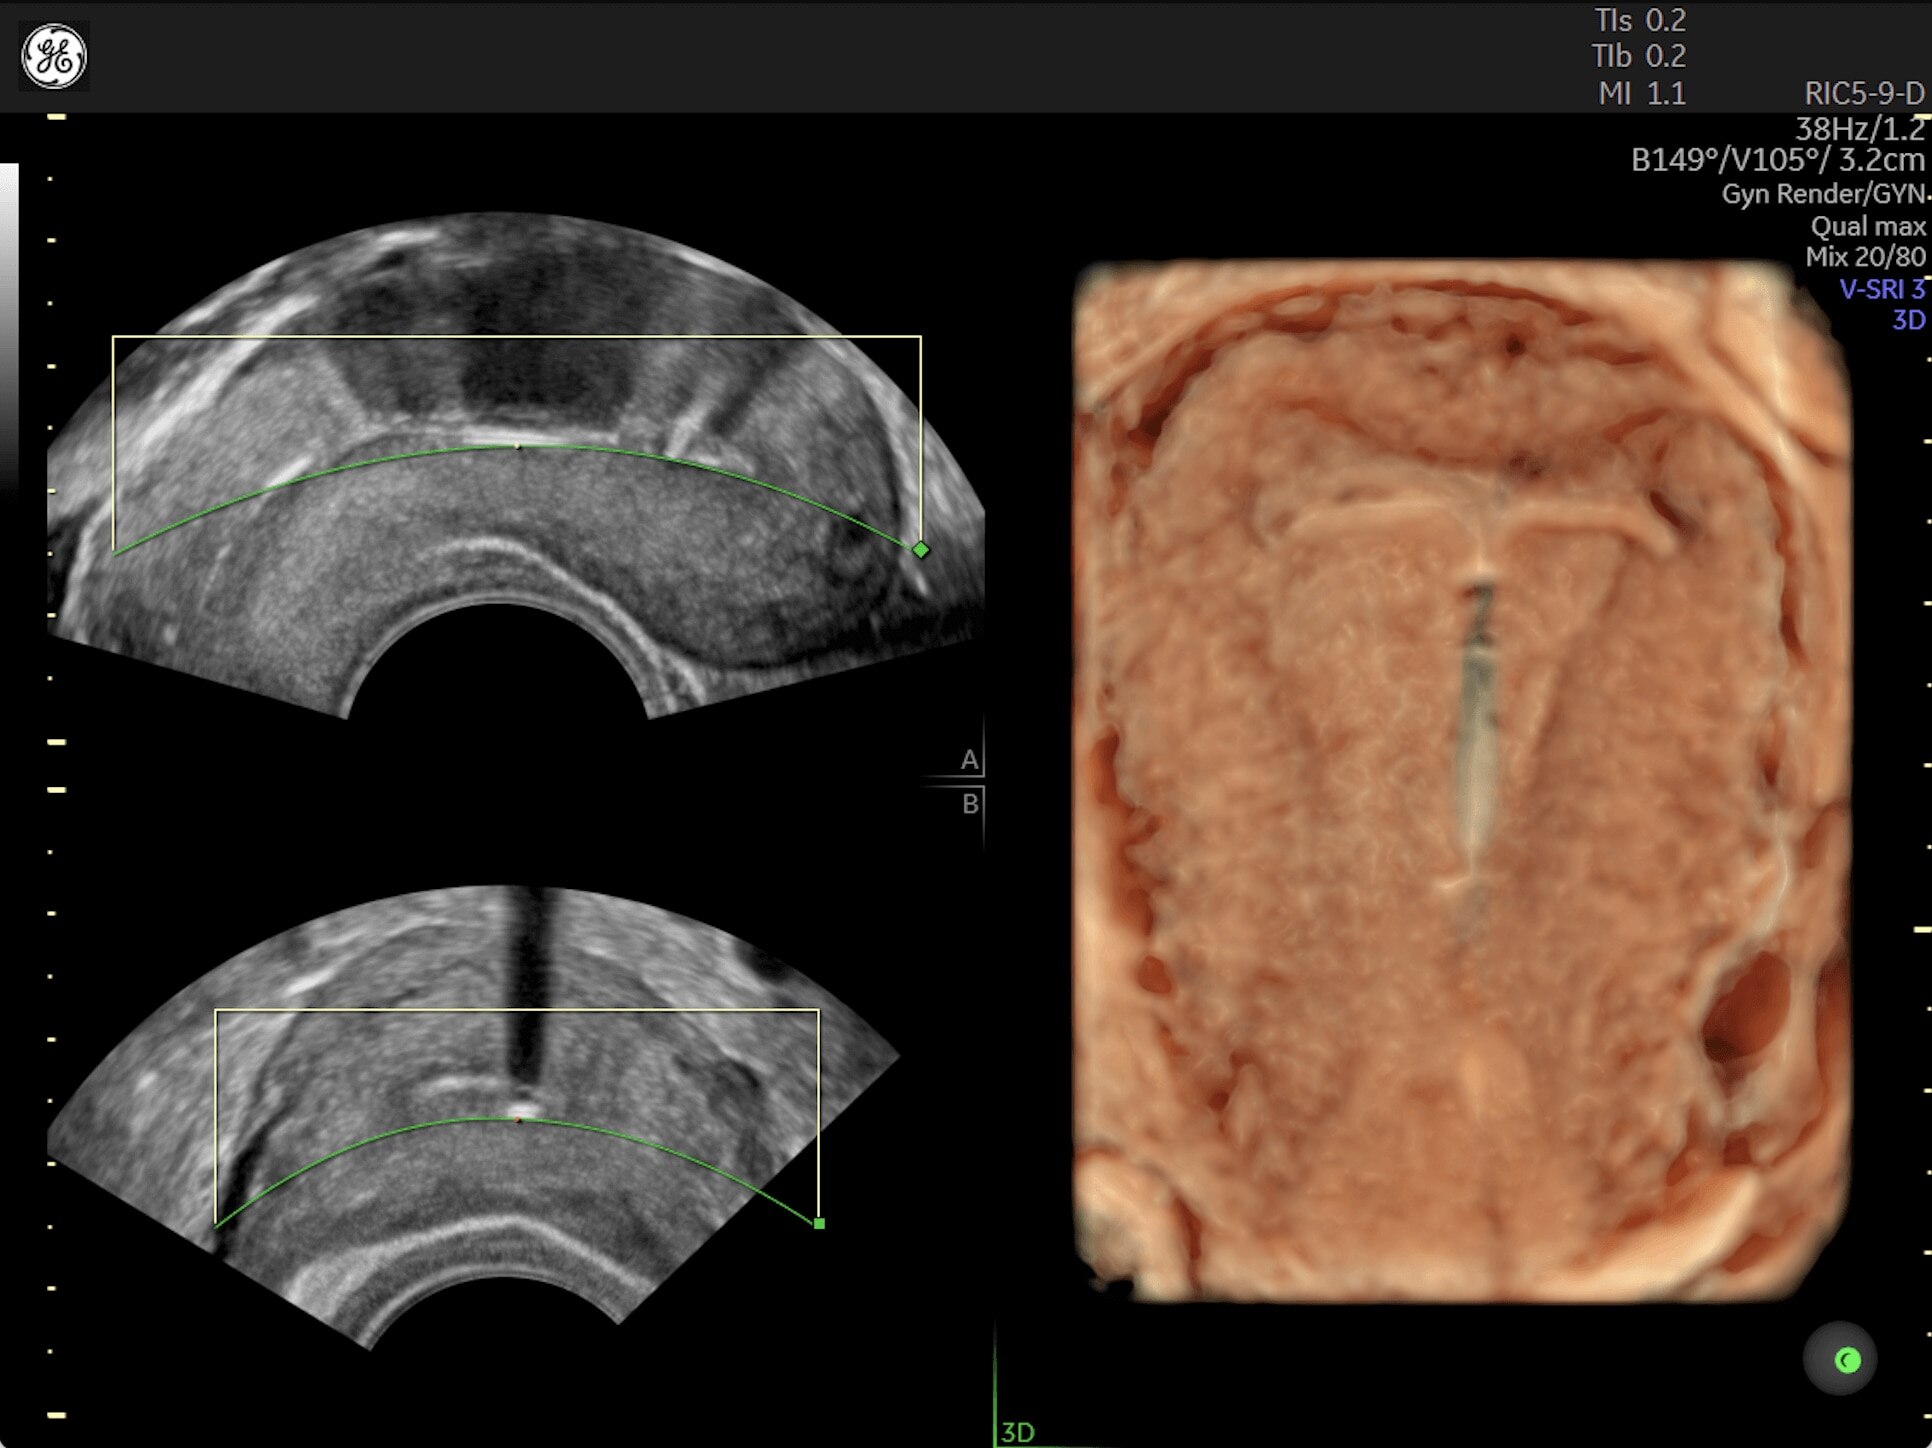

Generate spectacular 2D/3D and color Doppler images with increased penetration and stunning clarity, to help visualize critical details needed for diagnostic assurance. The Lyric Architecture unlocks new imaging and processing power to expand your imaging capabilities for years to come